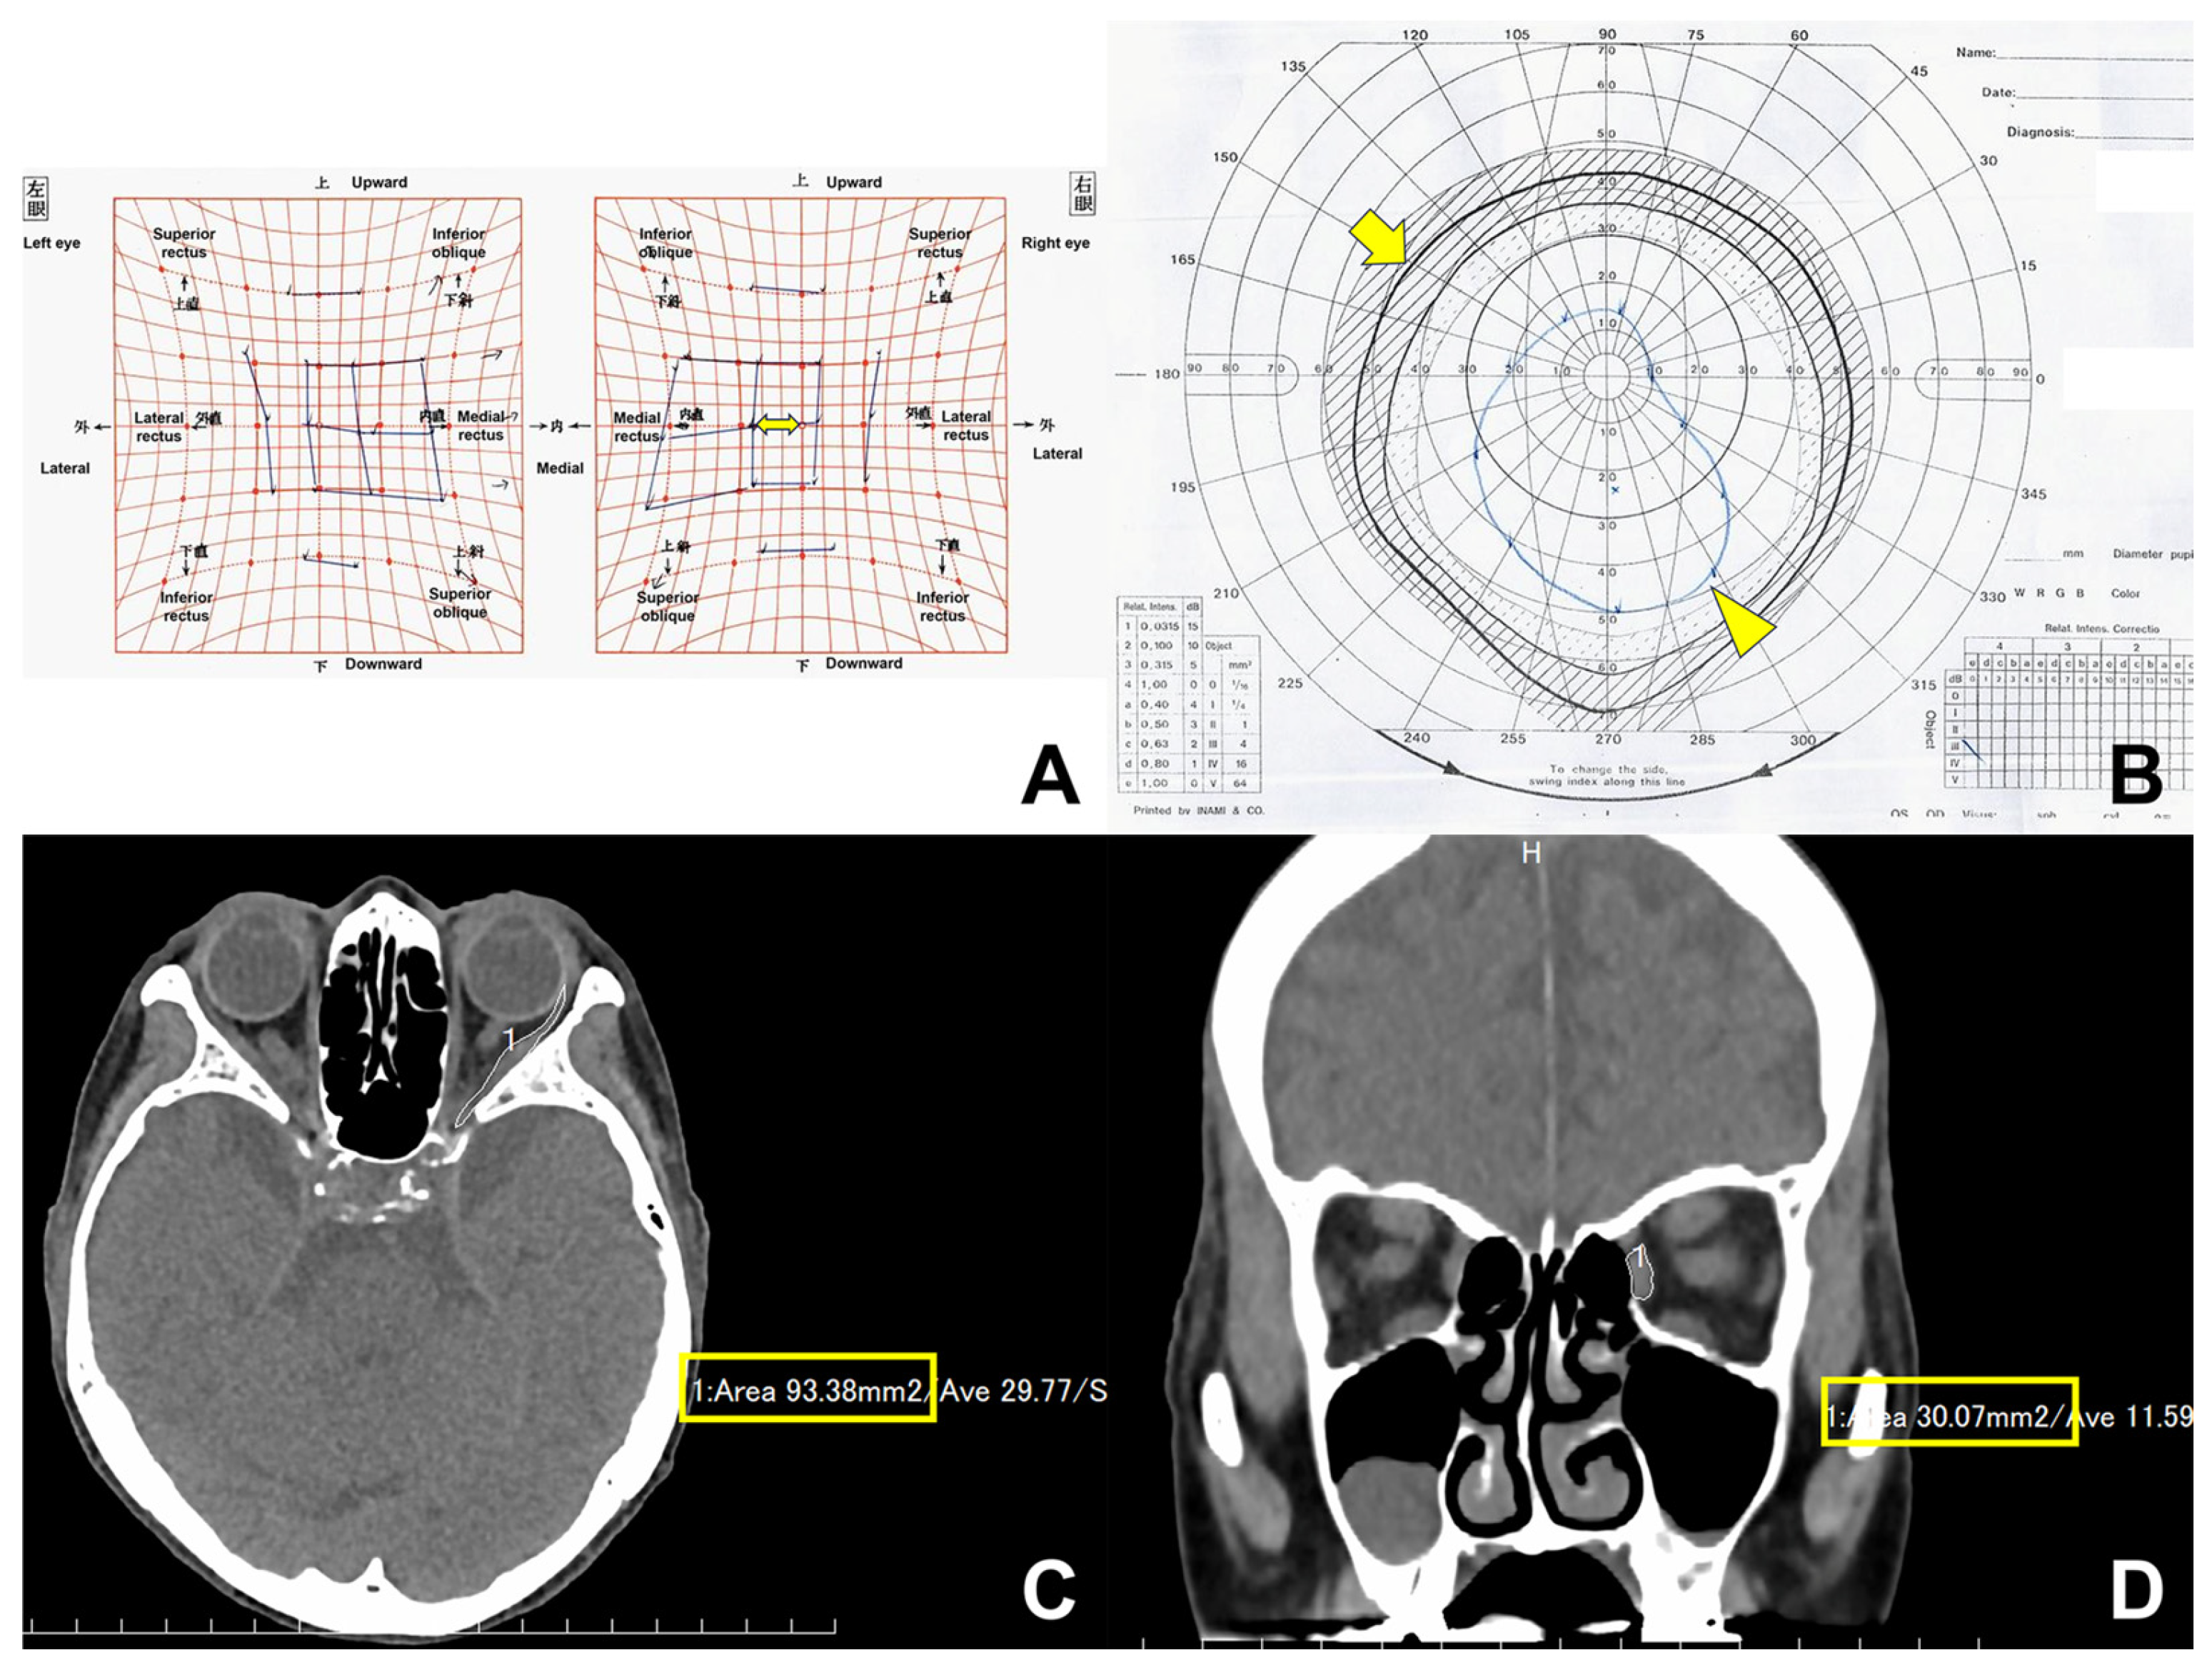

2.4. Computed Tomography (CT)

| Cross-sectional area of LR muscle | |||||

| Pre-decompression (mm2) | 154.0 ± 41.4 | 127.0 ± 34.6 | 139.2 ± 39.2 | 141.8 ± 41.6 | |

| Post-decompression (mm2) | 171.4 ± 45.9 | 131.8 ± 33.5 | 154.0 ± 45.3 | 149.2 ± 44.7 | |

| Increasing rate (%) | 13.2 ± 22.8 | 5.4 ± 18.6 | 11.4 ± 20.9 | 7.1 ± 21.3 | |

| p value | 0.019 | 0.335 | <0.001 | <0.001 | |

| Cross-sectional area of MR muscle | |||||

| Pre-decompression (mm2) | 55.1 ± 26.4 | 56.6 ± 28.8 | 59.2 ± 29.5 | 52.5 ± 25.2 | |

| Post-decompression (mm2) | 65.5 ± 31.1 | 72.7 ± 38.6 | 71.3 ± 33.6 | 66.9 ± 36.6 | |

| Increasing rate (%) | 20.4 ± 21.6 | 29.0 ± 39.9 | 22.9 ± 24.1 | 26.5 ± 38.9 | |

| p value | <0.001 | 0.004 | <0.001 | <0.001 | |